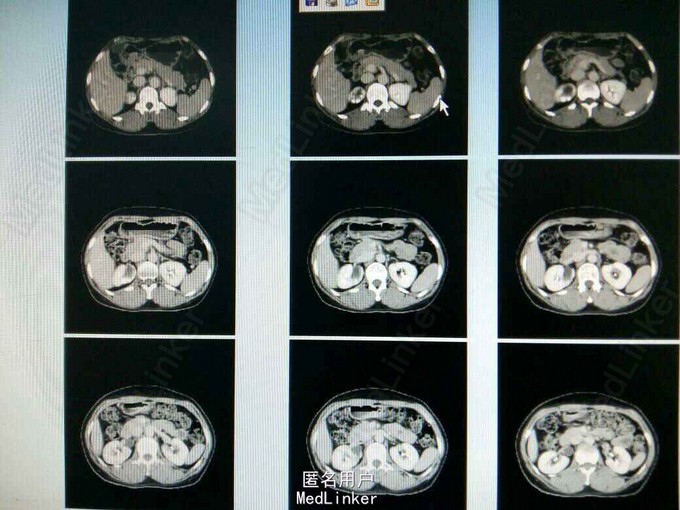

ct提示右侧双肾输尿管畸形,输尿管囊肿。总肾功能正常,尿常规正常,未发现结石等异常,右上位肾脏及输尿管扩张。